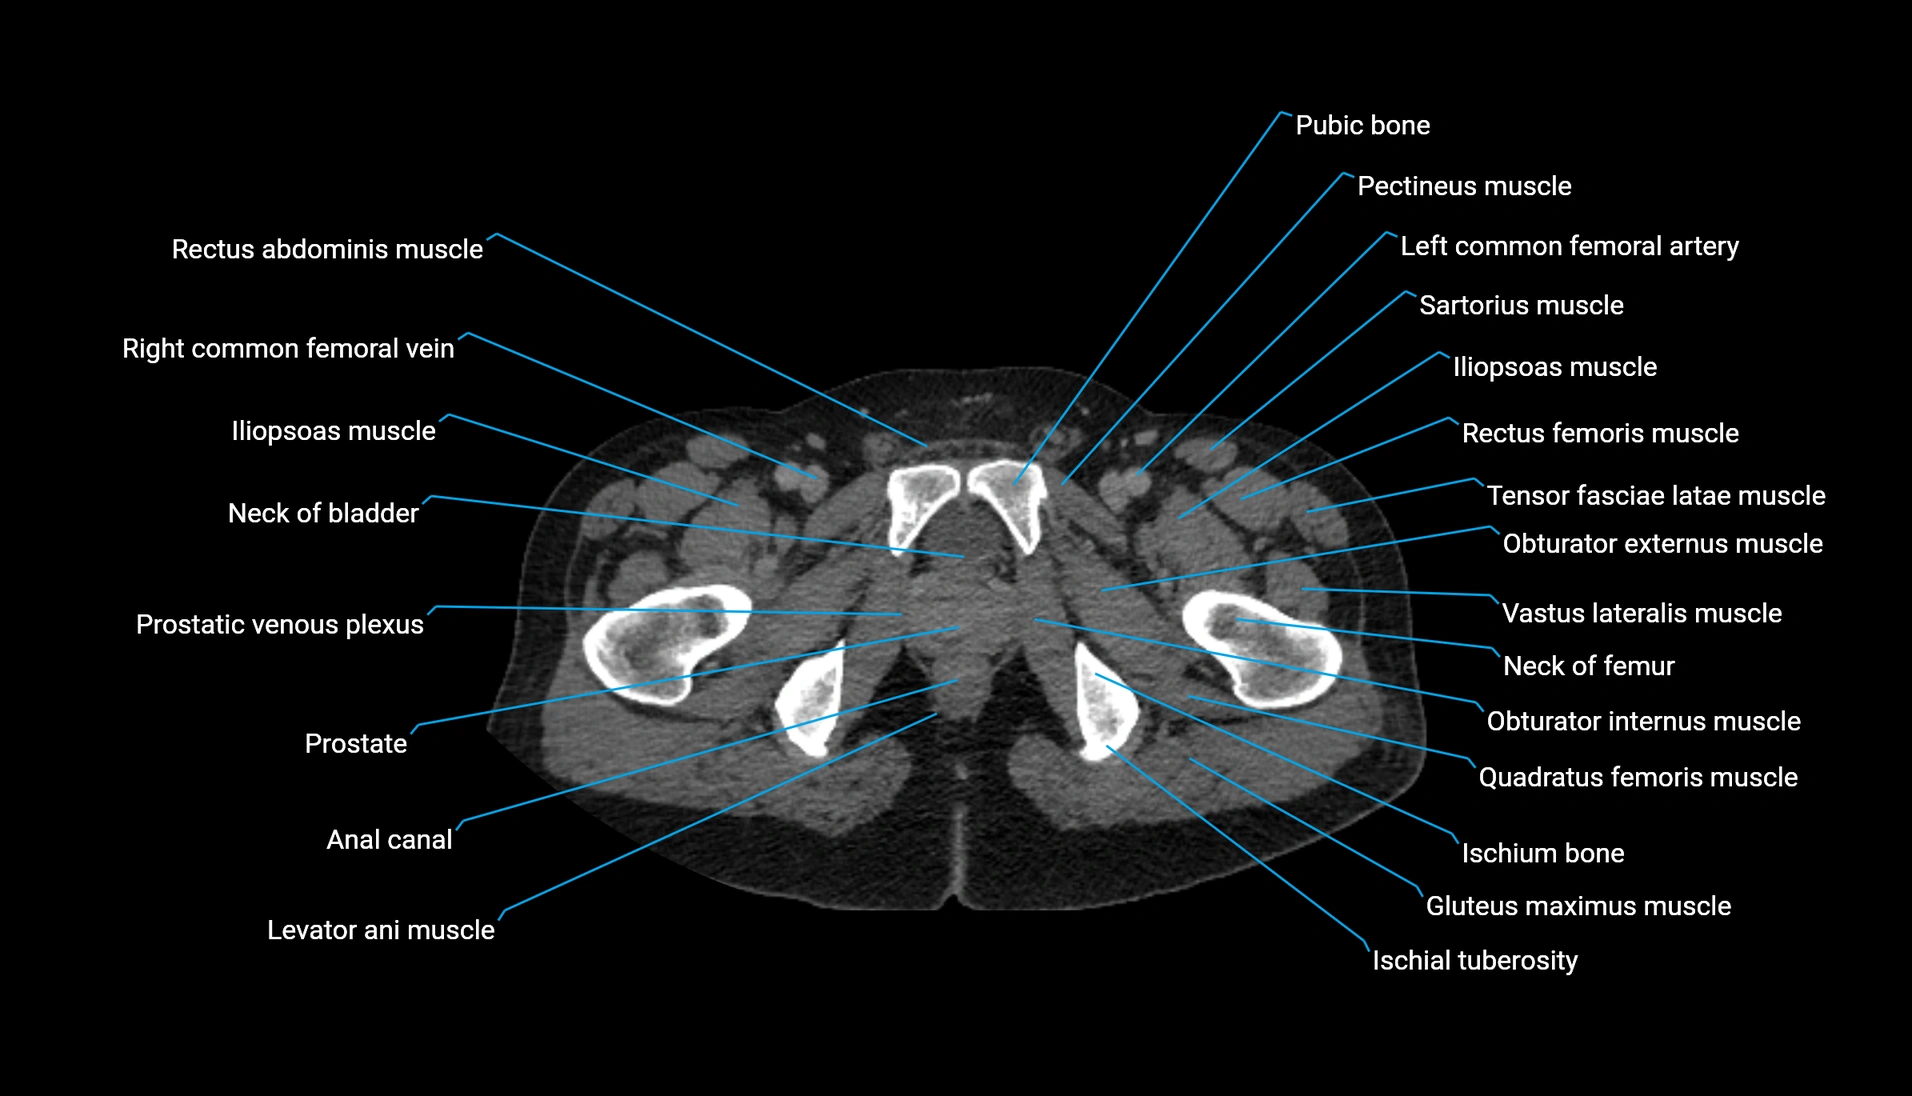

CT Appearance

Non-contrast CT:

-

Demonstrates cortical bone of acetabular rim in excellent detail

Detects fractures, dysplasia, retroversion, or bony overcoverage (pincer impingement)

3D reconstructions used in preoperative hip surgery planning

CT Post-Contrast (CT Arthrography):

Joint contrast outlines the acetabular labrum, cartilage, and margin

Demonstrates labral tears, cartilage defects, and subtle bony abnormalities

Alternative to MR arthrography in patients with MRI contraindications

CT VRT 3D image

CT image